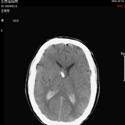

2).颅后窝血肿术前 术后

3).颅骨凹陷性骨折术前 术后